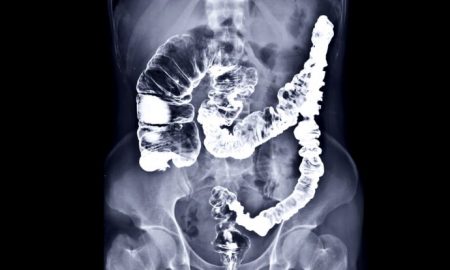

Da li ste znali da je rak debelog crijeva je treći najčešći rak u Velikoj Britaniji, ali je izlječiv ako se na...

Kašnjenje u postavljanju dijagnoze rakamože se pokazati smrtonosnim.